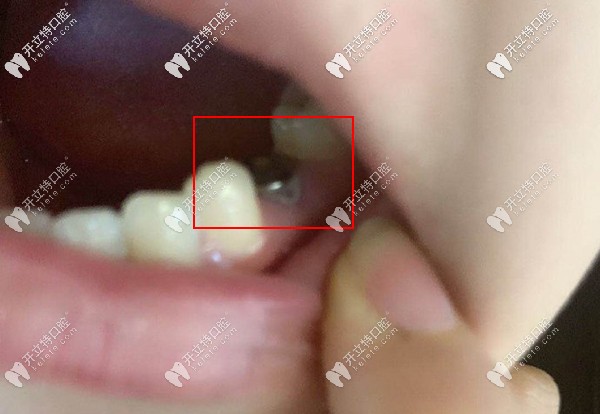

看看種植后的牙齒效果,擁有一口好牙真的是太nice了。

看看種植后的牙齒效果

種植反饋:主要是缺失的是咀嚼用的主要牙齒,還是要種上才能當(dāng)個(gè)快樂吃貨,選擇正規(guī)的醫(yī)院靠譜的醫(yī)生尤為重要,當(dāng)初她也是做了很多功課才選擇來德韓。